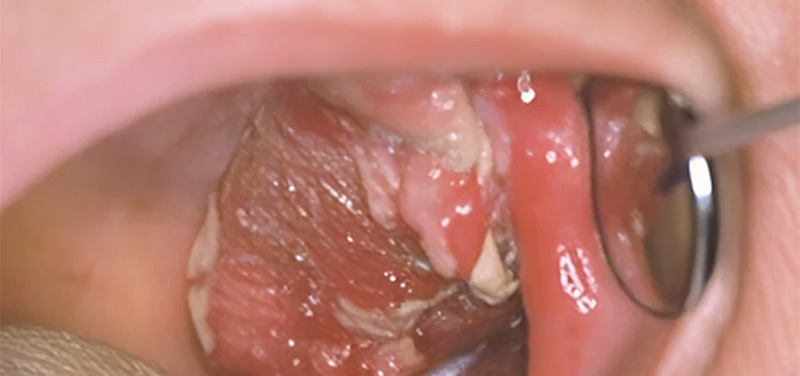

Fig. 03 : tumeur ulcéro-bourgeonnante du bord latéral de la langue.